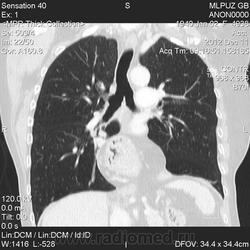

Cегодня выполнено РКТ брюшной полости, со слов врача проводившего исследование, справа в задних отделах определяется диафрагагмальная грыжа, содержимое которой составляют жировая клетчатка и верхний полюс правой почки; больших размеров фиксированная аксиальная грыжа пищеводного отверстия диафрагмы, где содежиться примерно половина желудка. Файлы исследования быдут выложены позже.

Добалены файлы КТ.

Обратите внимание, что на корональных реконструкциях полоска отделяющая забрюшинную клетчатку от лёгкого справа, значительно тоньше чем слева, потому как представляет из себя два листка плевры: париетальную и висцеральную. Слева она толще - потому как является диафрагмой. Также заметны края дефекта диафрагмы справа в области грыжевых ворот на короналах и сагиталах.

Добавлен протокол КТ грудной клетки.